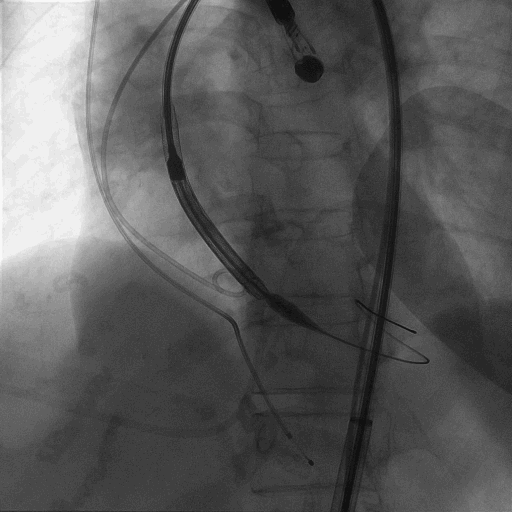

术中造影

植入L26 VenusA-Plus瓣膜,标准位释放,释放到2/3,观察瓣膜位置,以及再次确认冠脉风险,左冠正常显影,选择全部释放。